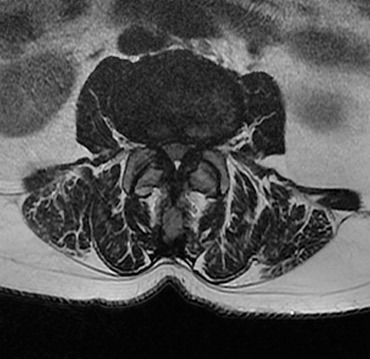

Εικόνα 1. Μαγνητική τομογραφία μεγάλου βαθμού στένωσης.

Η οσφυϊκή σπονδυλική στένωση (ΟΣΣ) χαρακτηρίζεται από πόνο στη ράχη και κυρίως νευρογενή διαλείπουσα χωλότητα με πόνο και κράμπες στα κάτω άκρα, δυσκολία στο βάδισμα και συχνά διαταραχές της ισορροπίας, αστάθεια και μουδιάσματα στα κάτω άκρα. Η πάθηση προκαλείται από εκφυλιστικές αλλοιώσεις στην οσφυϊκή μοίρα με τη μορφή διογκωμένων μεσοσπονδύλιων δίσκων, οστεοφύτων γύρω από τις αρθρώσεις και υπερπλασία των συνδέσμων. Ο συνδυασμός αυτός προκαλεί σταδιακά στένωση στο σπονδυλικό σωλήνα με προοδευτική πίεση στα νεύρα. Η ΟΣΣ αποτελεί τη συνηθέστερη χειρουργική ένδειξη στη σπονδυλική στήλη, παρουσιάζεται συνήθως σε ασθενείς μεγαλύτερης ηλικίας και σπανίζει σε άτομα κάτω των 50 ετών. Καθώς ο πληθυσμός γηράσκει και ταυτόχρονα αποκτά όλο και υψηλότερες απαιτήσεις για έναν πιο δραστήριο τρόπο ζωής, η σπονδυλική στένωση κερδίζει ολοένα το ενδιαφέρον της παγκόσμιας ιατρικής κοινότητας.